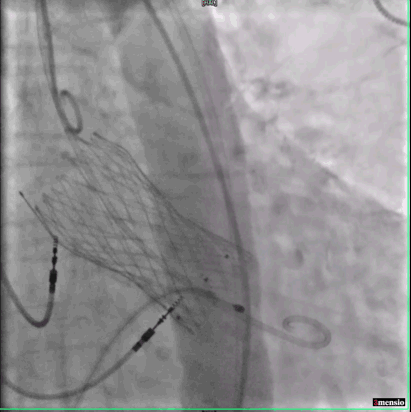

主动脉根部造影